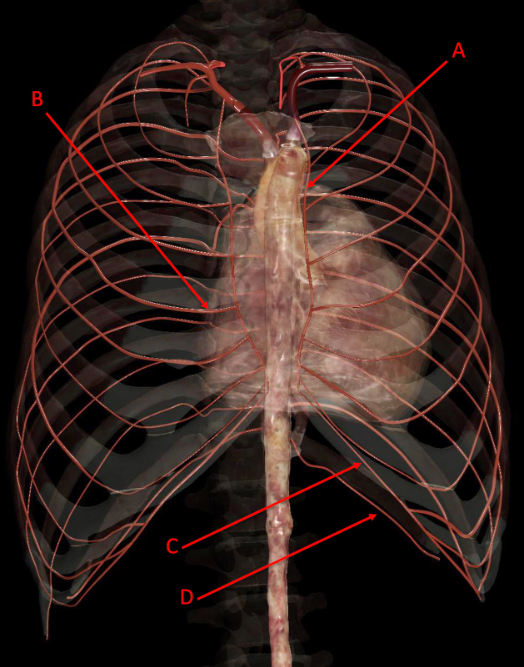

A. left internal thoracic artery

B. right anterior intercostal artery

C. musculophrenic artery

D. subcostal artery